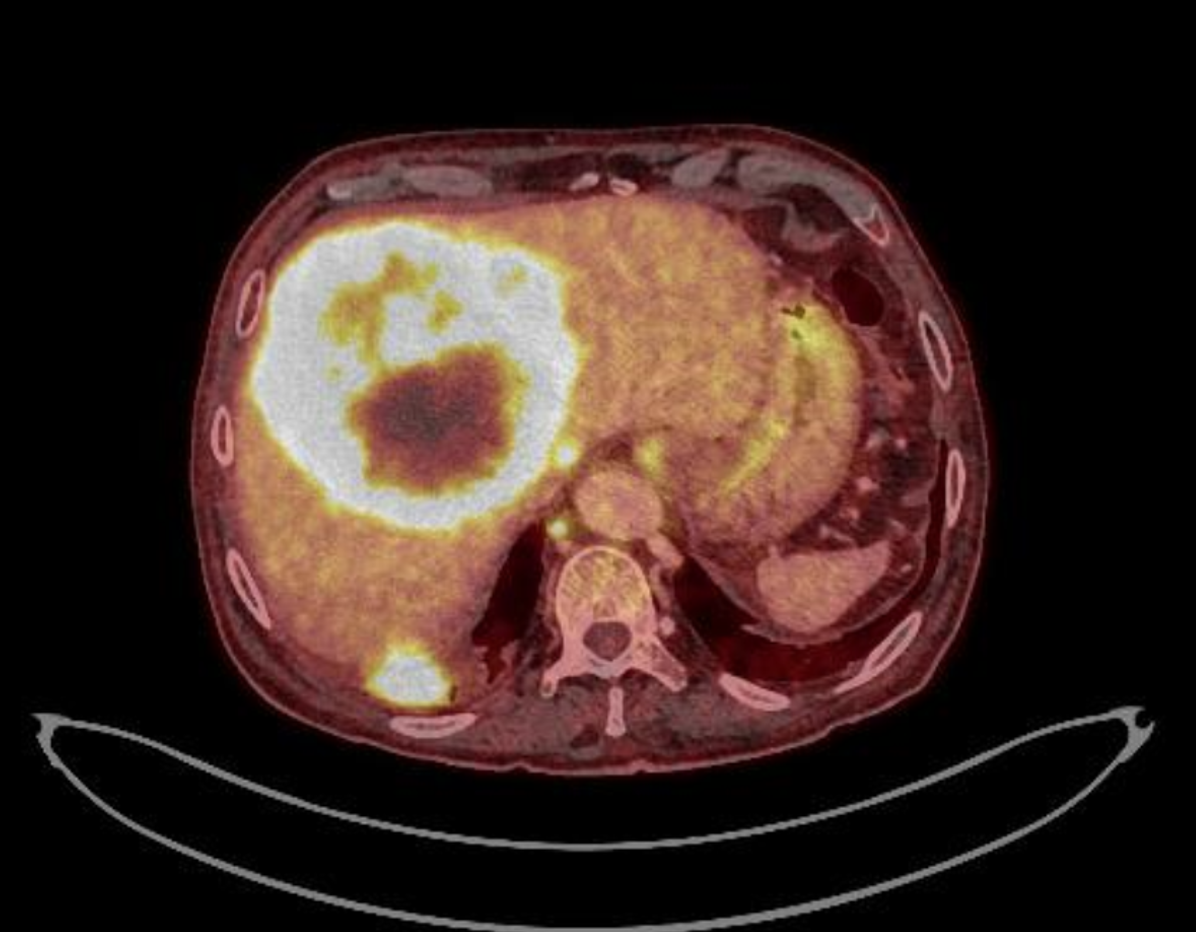

TAC body: Masa subcarinal que contacta con esófago. Hepatomegalia con 2 lesiones focales de gran tamaño en cúpula de 10 x 12 cm y segmento V-VI de 10 x 7,8 cm. Numerosas adenopatias retroperitoneales y en hilio hepático. Vesicula biliar con colelitiasis. Riñón izquierdo con 2 quiste corticales de gran tamaño (13 cm cada uno).

Fibrobroncoscopia: cáncer pulmonar lóbulo medio derecho. Atención Primaria: ca. microcítico de pulmón.

PET TAC: neoplasia pulmonar con gran cantidad de adenopatias supra e infradiafrágmaticas y depositos secundarios hepáticos.